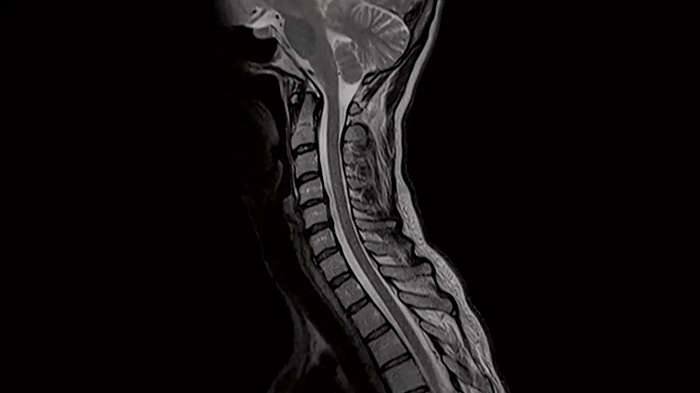

Spine

C-Spine - T2 TSE

Integrate Head/Neck and Spine Coil to gain outstanding C-Spine images with T2 TSE.

- Head/Neck Coil

- Spine Coil

Image Courtesy: University Hospital Erlangen, Germany | Image-ID: 4aaaa0440